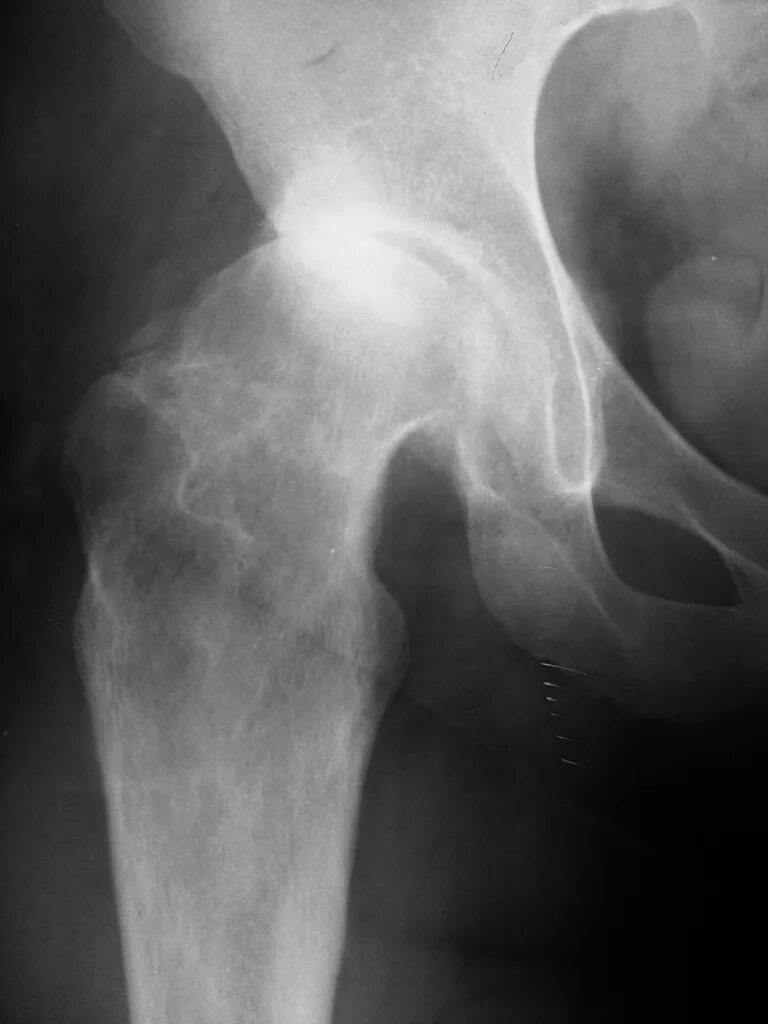

Коксартроз тазобедренного сустава 1 2